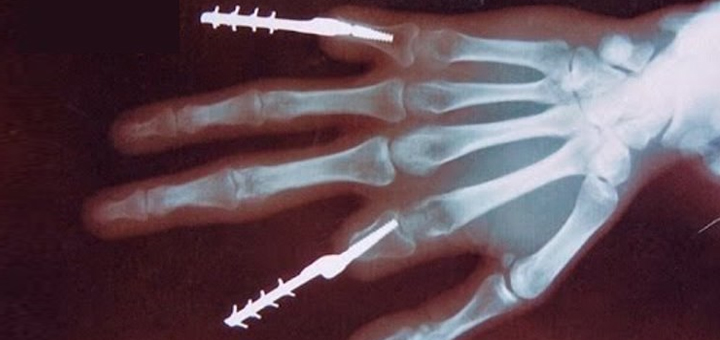

Пациент Российского научного центра им. Илизарова в Кургане уже более полугода живет с вживленным пальцем, который изготовлен по новой 3D-технологии…

Новейшее медицинское оборудование получила больница имени Баумана. Теперь специалисты центра патологии верхних конечностей могут проводить сложнейшие операции и возвращать пациентов…